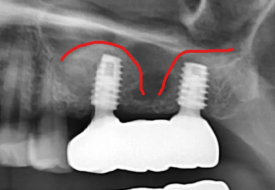

상악동 구조 파악을 위한 CT

또한 왼쪽 위 어금니는 발치 후 잇몸뼈가 부족뿐만 아니라, 상악동이라는 공기주머니와 가까운 위치에 있어 측면 접근법 상악동 거상술이라는 난도 높은 수술과 임플란트 골이식이 필요했는데요.

빨간선이 상악동 위치

이 과정은 상악동의 얇은 막을 조심스럽게 들어 올려 인공 뼈를 이식하는 매우 정교한 기술로 수술 경험과 전문성이 필요한 시술이지만,

상악동거상을 위해 측면 골을 열고 조심스럽게 올리는 모습

상악동 위치를 바꾸고 이공뼈 이식

임플란트 식립

상악동 위치

안정적으로 이식된 인공뼈

왼쪽 위 어금니는 발치 후 골이식과 상악동 거상술을 함께 시행했습니다.

수술 후 엑스레이에서 상악동이 인공 뼈로 채워진 모습이 확인되었고, 임플란트가 안정적으로 자리 잡았습니다.